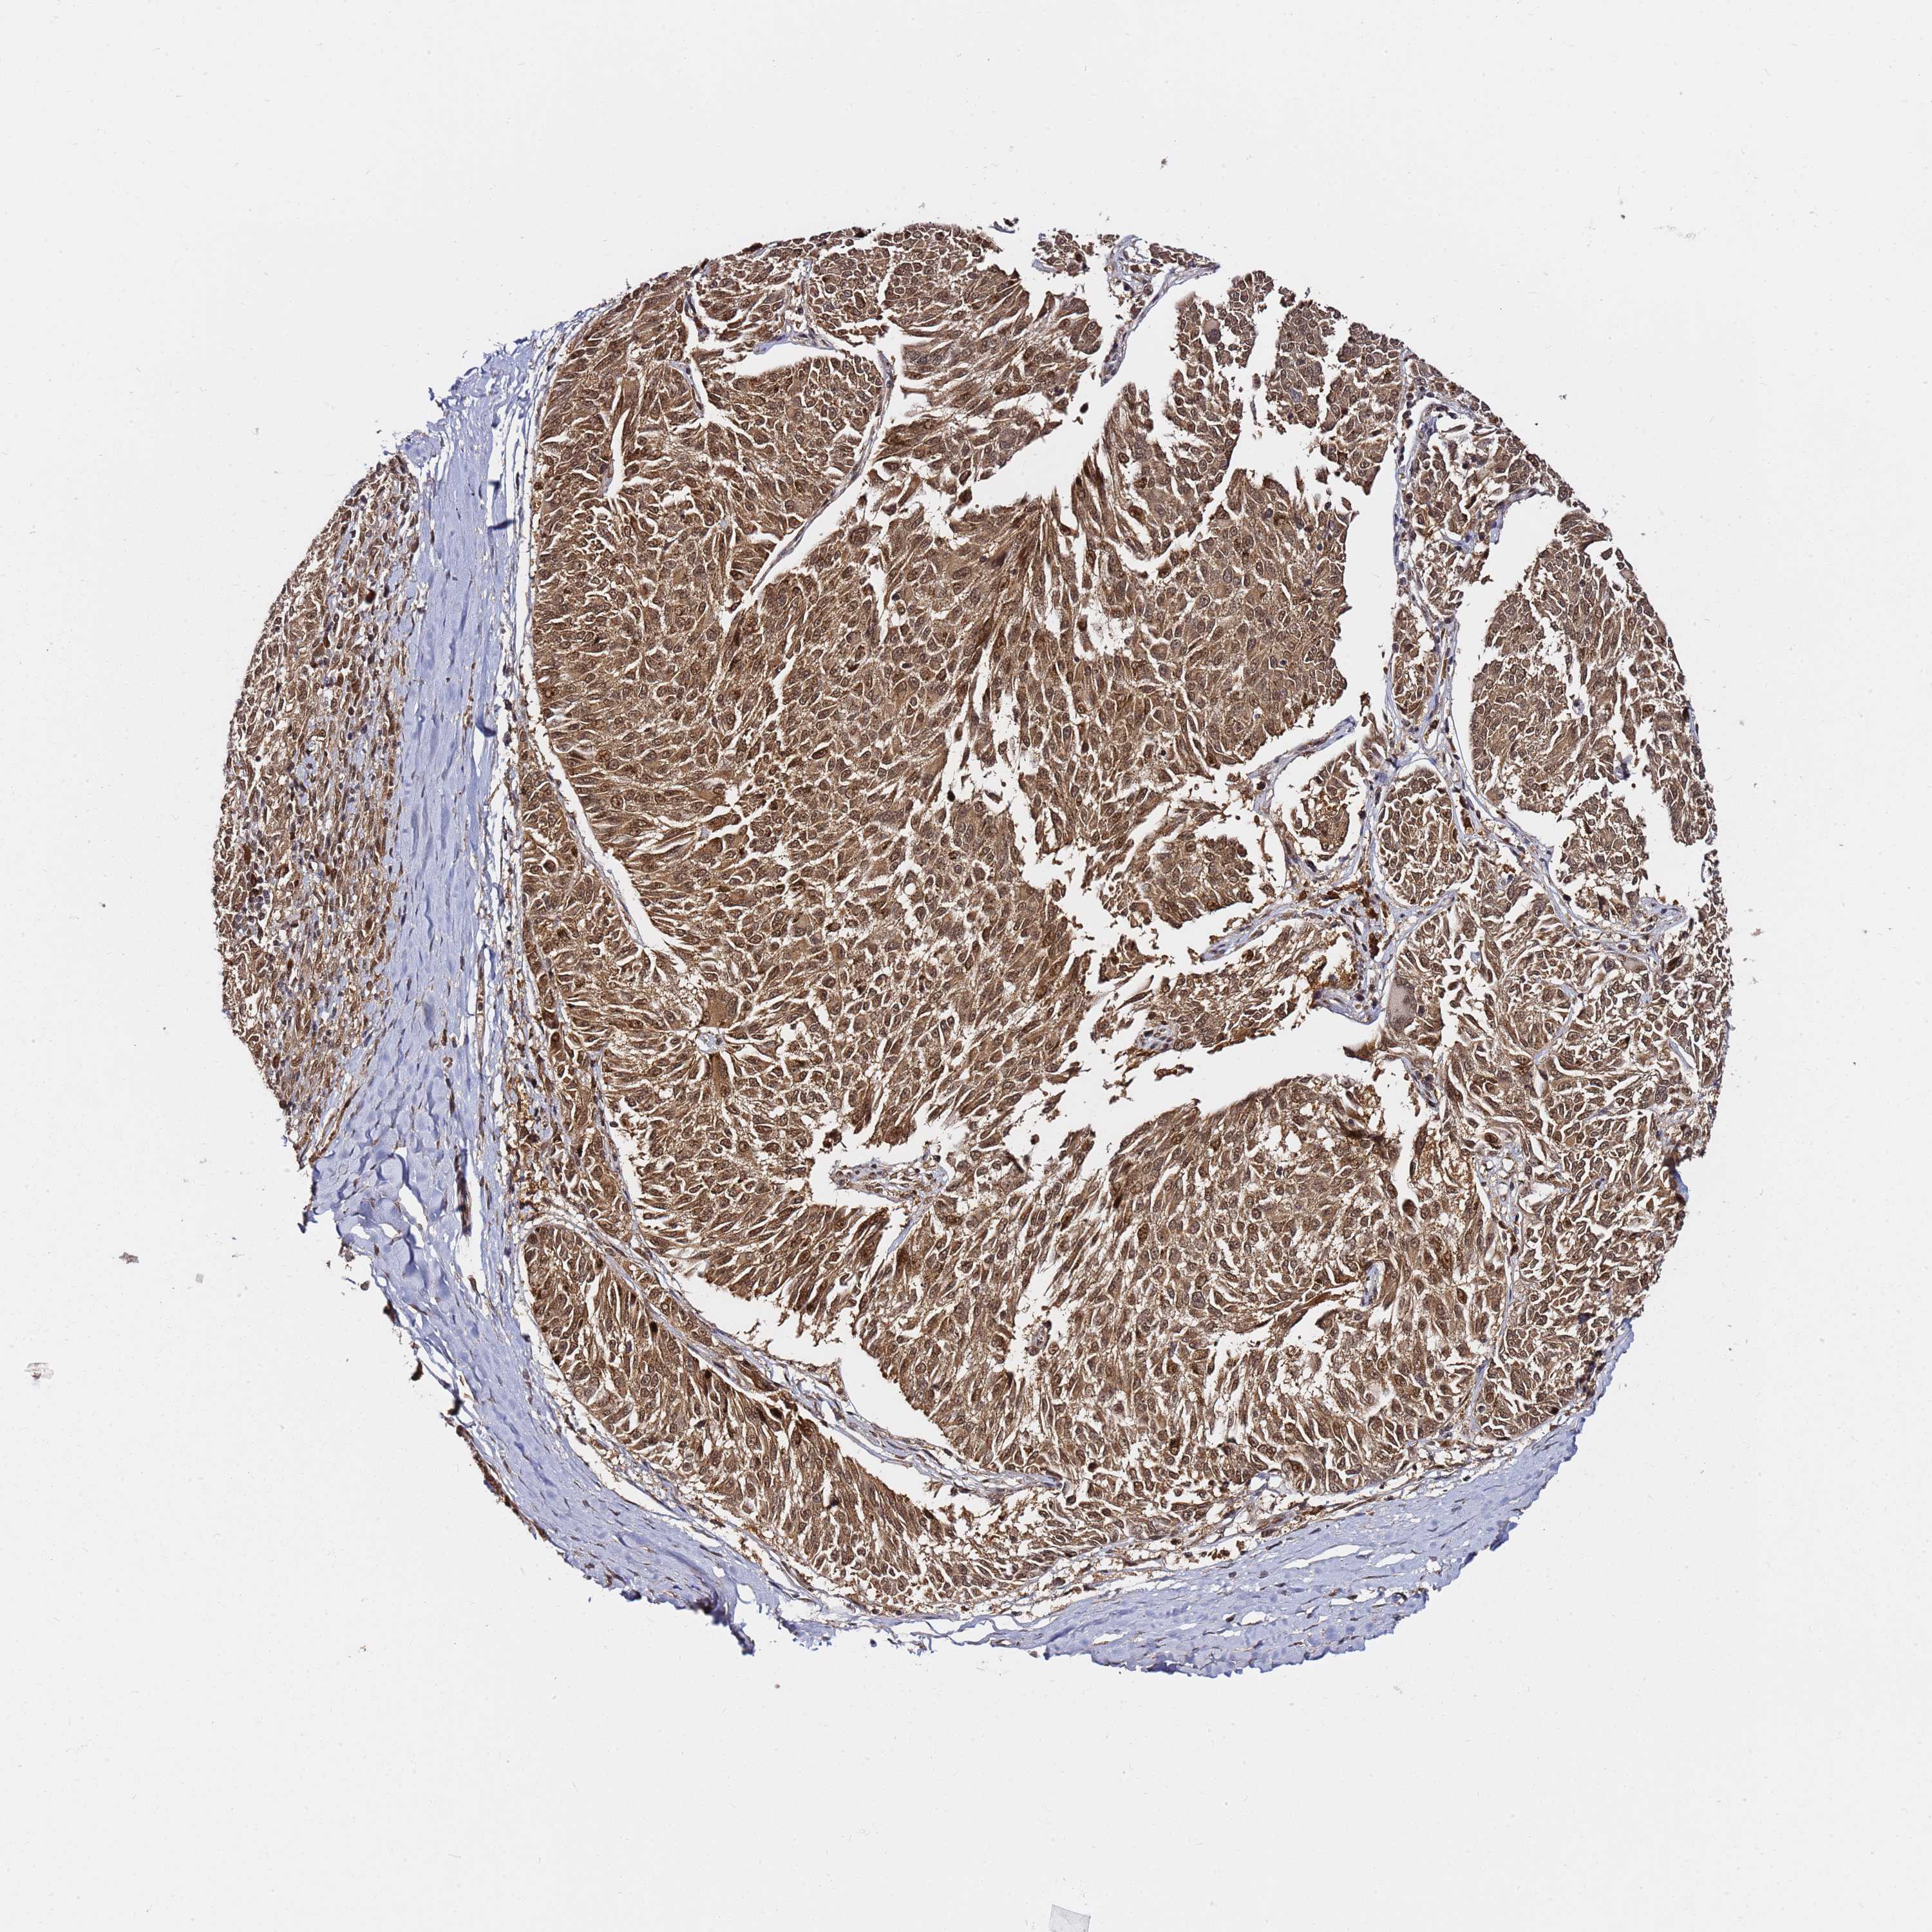

MELANOMA - Protein expressioni

A mouse-over function shows sample information and annotation data. Click on an image to view it in a full screen mode. Samples can be filtered based on level of antibody staining by selecting one or several of the following categories: high, medium, low and not detected. The assay and annotation is described here.

Note that samples used for immunohistochemistry by the Human Protein Atlas do not correspond to samples in the TCGA dataset.

Antibody stainingi

Antibody staining in the annotated cell types in the current human tissue is reported as not detected, low, medium, or high, based on conventional immunohistochemistry profiling in selected tissues. This score is based on the combination of the staining intensity and fraction of stained cells.

Each image is clickable and will lead to virtual microscopy that enables deeper exploration of all samples and also displays staining intensity scores, fraction scores and subcellular localization as well as patient and tissue information for each sample.

Antibody HPA045780

Staining

High

Medium

Low

Not detected

Intensity

Strong

Moderate

Weak

Negative

Quantity

>75%

75%-25%

<25%

None

Location

Nuclear

Cytoplasmic/membranous

Cytoplasmic/membranous,nuclear

Malignant melanoma, NOS